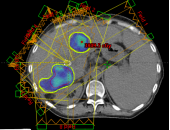

病例展示二:前列腺癌

XXX,男,64岁,主诉:间断性会阴部疼痛10月,确诊为前列腺癌7月。盆腔核磁:前列腺偏左侧异常强化占位,多考虑前列腺Ca,并左侧精囊腺受侵可能,盆腔左侧略大淋巴结。前列腺癌标志物提示:TPSA 88.67 ng/ml,FPSA 3.84 ng/ml。病检:(前列腺穿刺组织左侧)前列腺腺泡腺癌,Gleason评分4+3=7分;(前列腺穿刺组织右侧)Gleason评分3+3=6分。诊断:1、前列腺恶性肿瘤 双侧 腺泡腺癌Gleason评分4+3 =7分 cT3bN0M0 III期 KPS评分:80分。治疗方案:醋酸戈舍瑞林缓释植入剂 10.8mg 皮下注射、比卡鲁胺胶囊 50mg 口服 1次/天”全身治疗,并行前列腺癌碳离子治疗,剂量:57.6 Gy(RBE)/16 Fx。